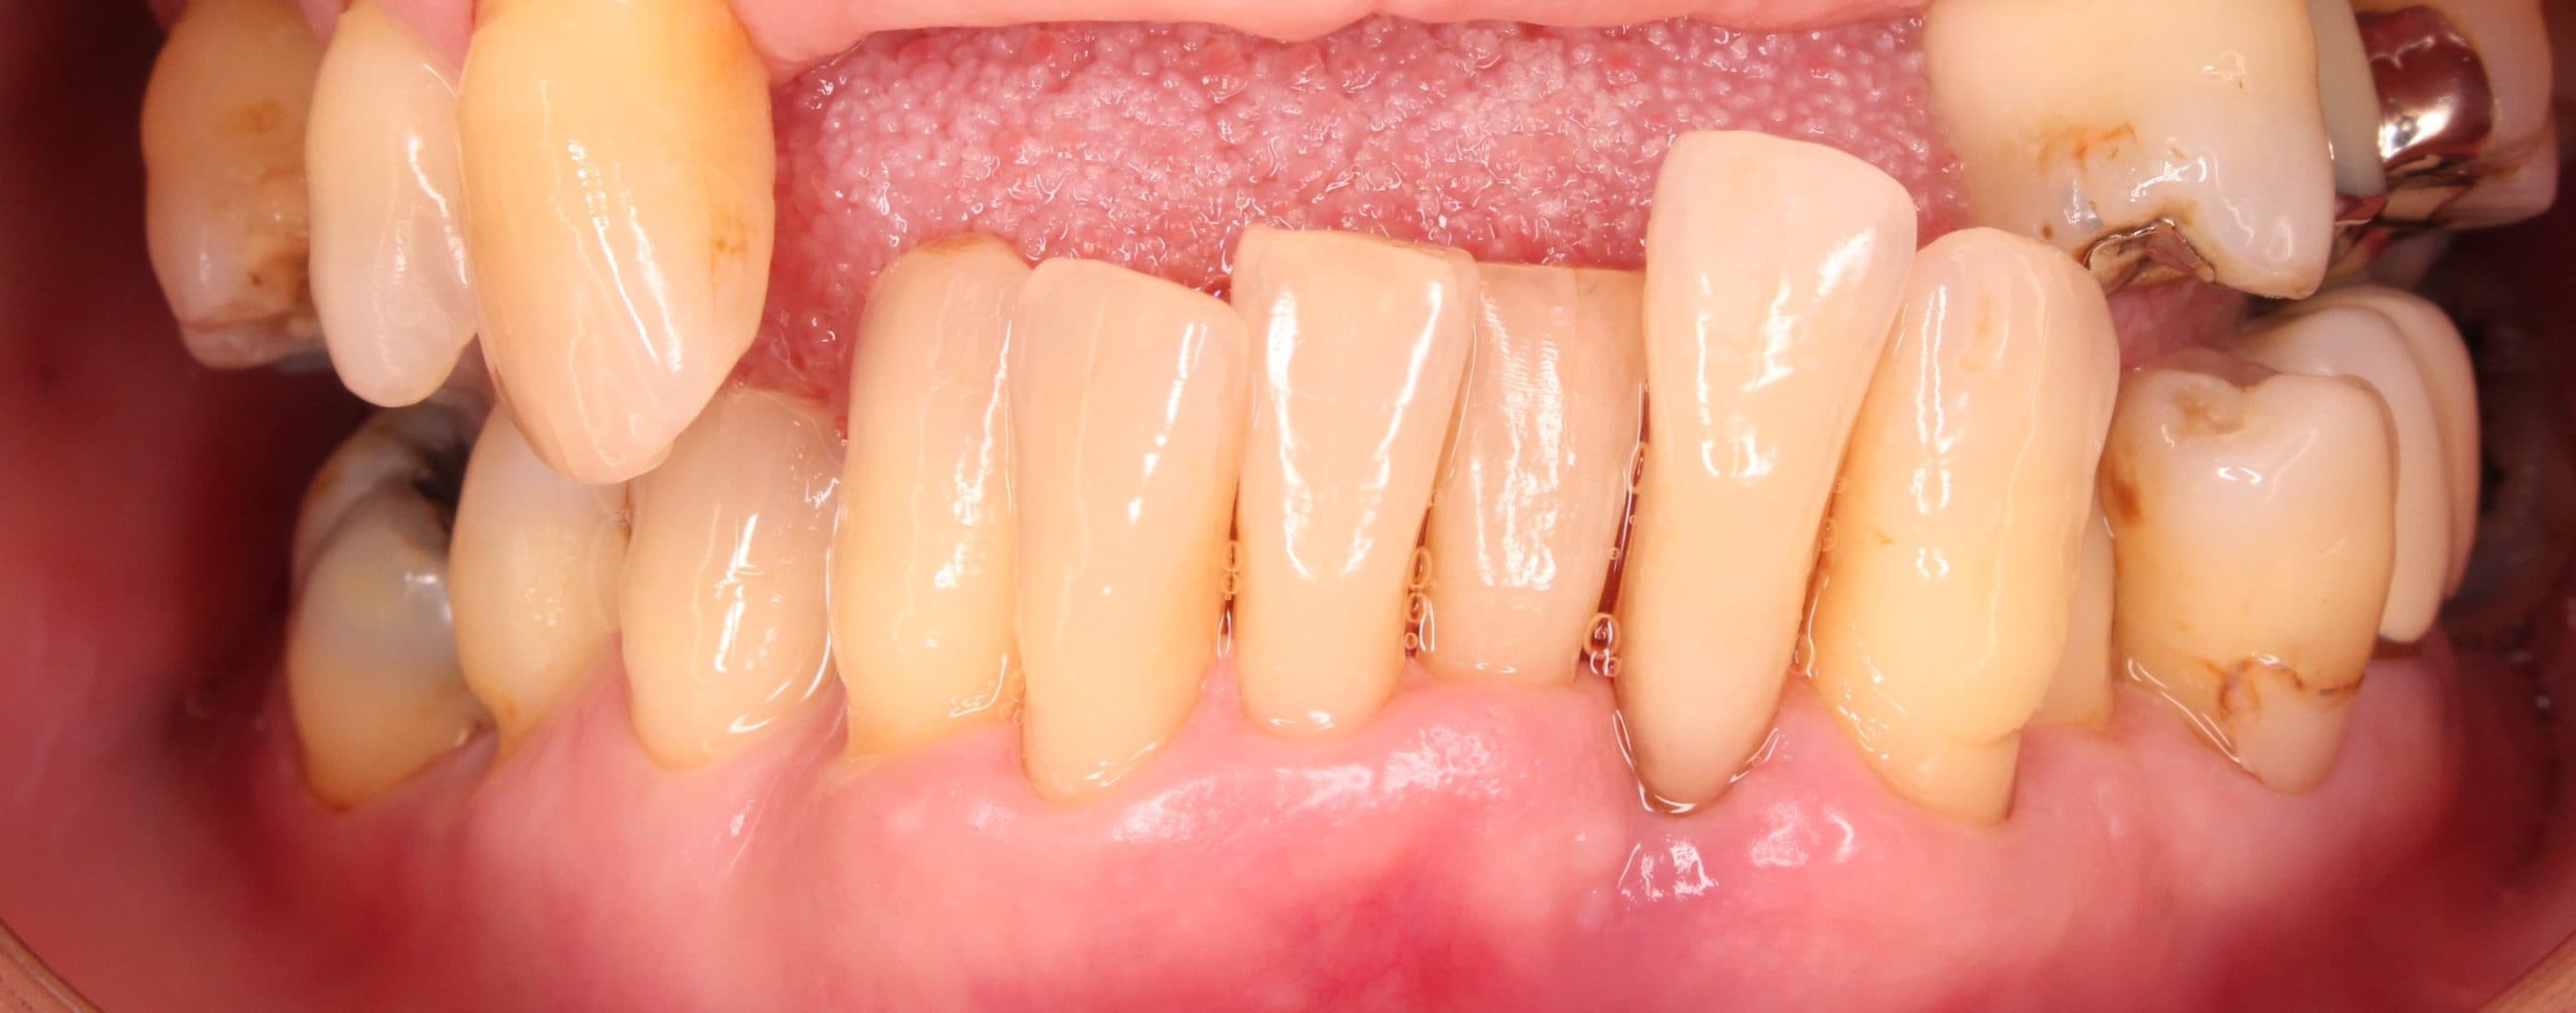

術後

術前

歯肉にのっているだけの歯の動きを完全に止める事は出来ませんが、治療後は日常の不便も無く、生活を送れるとのことでした。

可能な限り、現状維持が長く続くよう1か月に1度のメインテナンス管理を行っていきましょう!